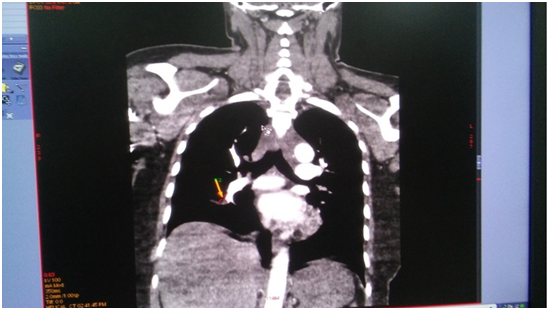

On the next day, at the day time, she felt progressive dyspnea. She was transferred to the intensive care department, where the suggestion of acute lung artery thromboembolic was taken, taken into account the character of dyspnea and extremely low level of blood saturation 60%, with weak response to oxygen therapy. The suggestion was approved by the chest tomography, where the thrombosis of both central lung arteries was revealed (Figure 1-4). After the short discussion among the colleagues, the procedure of thrombolysis was performed. We considered the extremely bad condition of the patient, weak response to oxygen therapy, young age and a kind of the operation. There were no pass to any cavity, no anastomosis, the inserted drainage system, to let blood flow out. Additionally, we had blood cell-save machine “Haemonetics Cell Saver 5+” (USA) to reinfuse blood and decrease blood loss.

Figure 2 (CT of thromboembolism in the right LA).